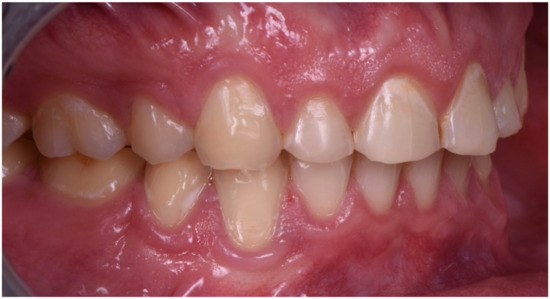

2. Clinical Report

2.1. Planning Phase